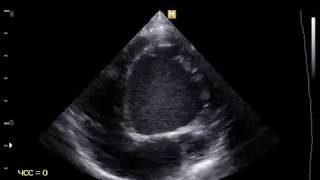

Экокардиография Дилатационная кардиомиопатия

Михаил Михненков

Дилатационная кардиомиопатия

Дилатационная кардиомиопатия Дилатационная кардиомиопатия — заболевание миокарда, характеризующееся развитием дилатации полостей ...

Wikitube Ru